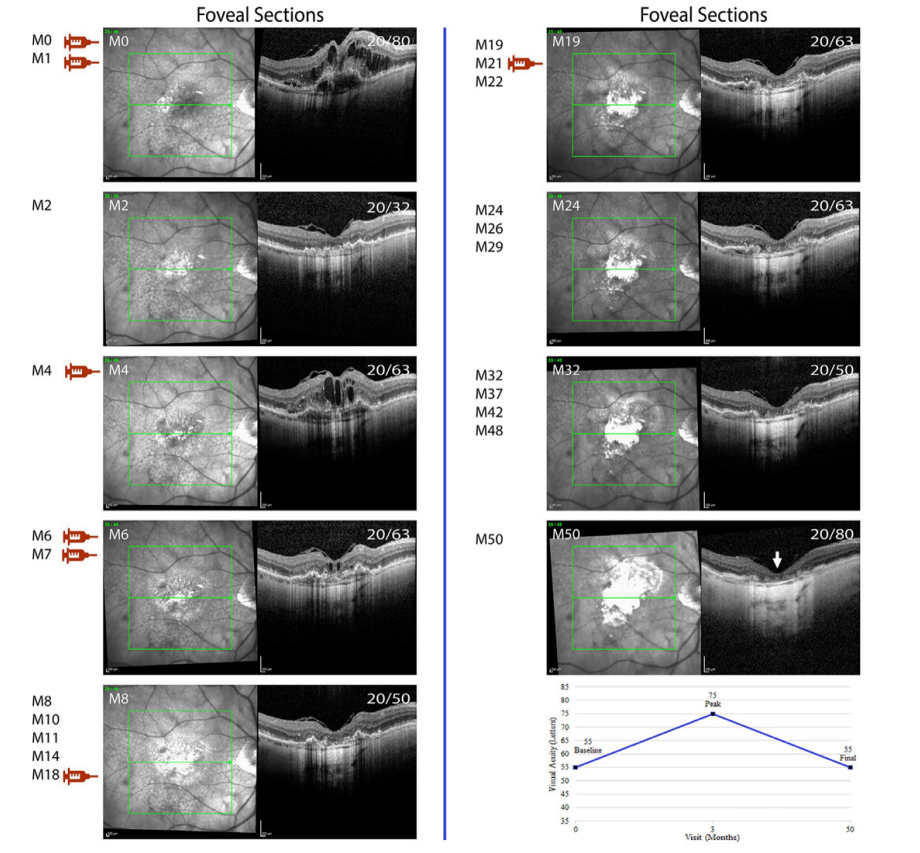

图 1 最后一次注射抗VEGF药物43个月后,血管性色素上皮脱离消退继发黄斑萎缩

Figure 1 Development of macular atrophy following collapse of a vascularized pigment epithelial detachment 43 months after the last anti-VEGF injection

Infrared (IR) images and horizontal spectral domain optical coherence tomography (SD-OCT) scans through the fovea from subject 8 who developed subfoveal atrophy from regression of vascularized pigment epithelial detachment. Top left corner shows follow-up visits in months (M) and top right corner shows Snellen visual acuity. Injection symbols (red: aflibercept) show the visits at which anti-VEGF injection was administered. Line graph shows baseline, peak and final visual acuity in letters.